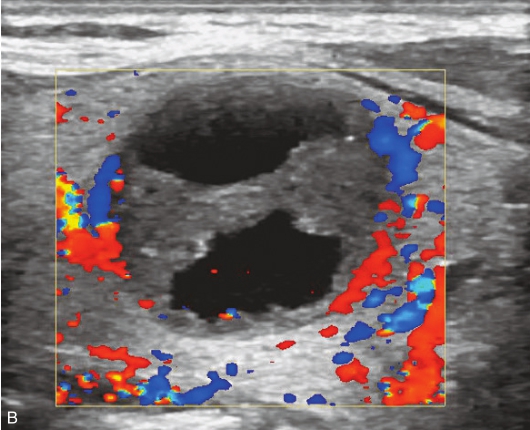

甲状腺右叶中部可见一囊实性结节,大小约2.1cm×1.8cm×1.5cm,形状尚规则,边界尚清楚,分布不均匀,后方回声无变化,CDFI显示结节内可见丰富的血流信号,见图1-3-20。

图1-3-20 甲状腺腺瘤伴囊性变示意图

A.甲状腺右叶纵切面示甲状腺右叶中下部囊实性结节,形态规则,边界清楚;B.CDFI显示其内部分可见丰富的血流信号,部分未见血流信号

注射造影剂后,12s病灶实性部分稍晚于周围甲状腺组织开始增强,病灶增强模式为等增强,增强形态为不均匀增强,15s病灶实性部分增强达峰值,20s病灶实性部分增强开始减退,35s病灶实性部分呈不均匀低增强,整个造影过程中病灶内囊性部分始终呈无增强,见图1-3-21、ER1-3-10。

(1)病灶内实性部分同步或先于周围甲状腺组织开始增强。

(2)病灶内实性部分增强为高增强或等增强。

(3)病灶内囊性部分在造影过程中始终呈无增强。

甲状腺腺瘤囊性变超声表现为实性或混合回声,腺瘤囊性变在囊液吸收后,体积逐渐缩小,超声显像时,回声会从混合回声变为低回声,超声表现易与甲状腺癌混淆,超声造影可以明确病灶内始终无增强,从而提高诊断准确性。

图1-3-21 甲状腺腺瘤伴囊性变造影图像

A.注入造影剂12s;B.注入造影剂15s;C.注入造影剂20s;D.注入造影剂35s